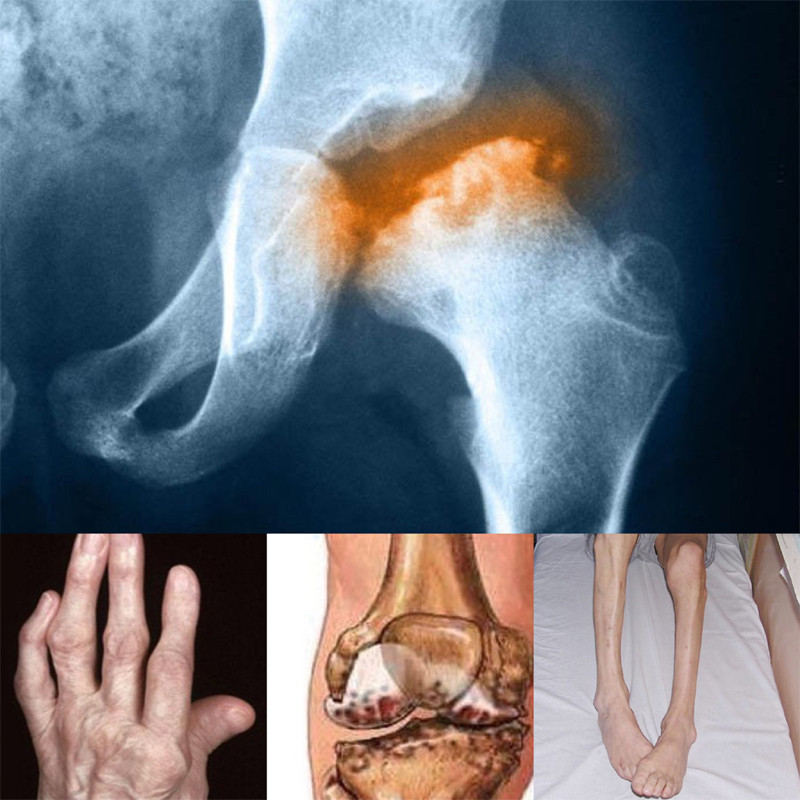

Thoái hóa khớp là một bệnh lý mạn tính, đặc trưng bởi những tổn thương tại sụn (nứt vỡ, bào mòn) và xương dưới sụn cùng với những thay đổi khác của khớp như hẹp khe khớp, gai xương.

Nếu không được điều trị sớm và đúng cách, thoái hóa khớp không chỉ gây đau nhức mà còn gây ra nhiều biến chứng nguy hiểm khác cho người bệnh như: hoại tử xương hoặc gãy xương; cong, lệch, biến dạng khớp; chảy máu hoặc nhiễm trùng trong khớp; teo cơ do bệnh nhân bị hạn chế vận động. Ngoài ra, thoái hóa khớp còn gây ra các biến chứng khác như: rối loạn giấc ngủ, giảm năng suất làm việc, chứng vôi hóa sụn khớp, lo âu…